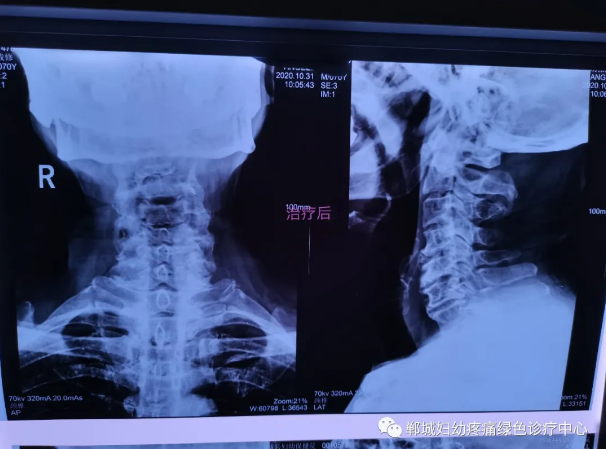

治疗前李老师颈椎X线检查影像

1个疗程治疗后颈椎X线检查对比